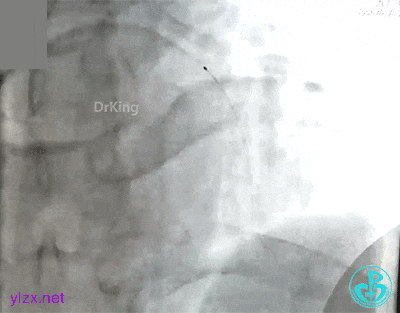

抽吸导管反复抽吸无效,前降支近端血栓无明显改变。送入Guidezilla,进入血栓部位,10ml注射器反复抽吸,抽出了类似脂肪组织样的物质。